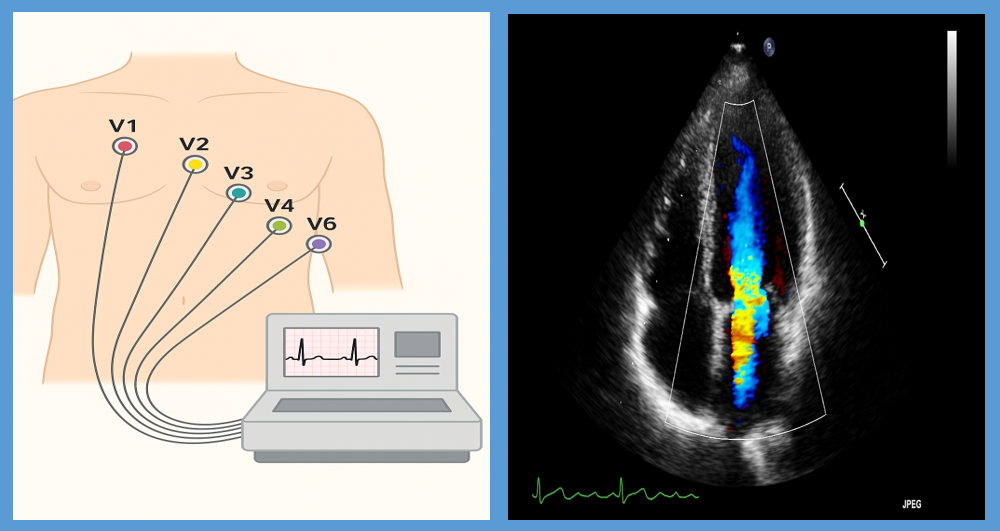

심장의 전기신호를 확인하는 기본 검사입니다.

가만히 있을 때는 정상이라도, 운동 중 심전도 변화가 생기면 협심증을 의심할 수 있어요.

→ 운동부하 심전도라고 해서 러닝머신에서 걷거나 뛰며 검사하는 경우도 많아요.

초음파로 심장의 구조와 움직임을 살펴봐요.

심장이 혈액을 잘 내보내고 있는지, 벽이 고르게 움직이는지 등을 확인해

간접적으로 혈류 장애를 판단할 수 있어요.